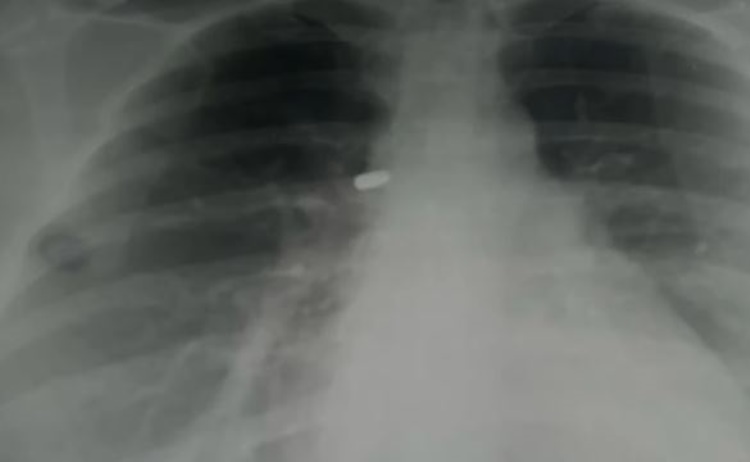

Doctors then discovered that she was not stabbed at all but was actually hit by a pellet-shaped bullet. The bullet is still lodged in her back, and doctors have not yet removed it because of its sensitive position.

For now, she has been given medicine, including an anti-tetanus shot, while waiting for the safest time for surgery.